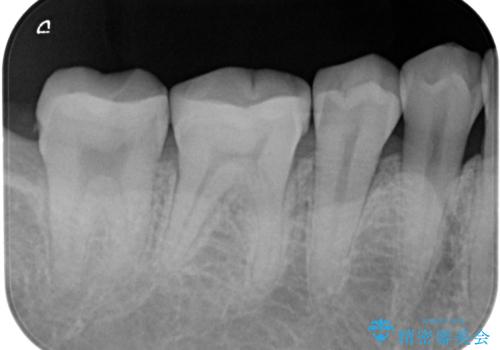

- セラミック治療希望の患者様です。

古い樹脂の材料をとりe-maxの詰め物で治療を行いました。

適合の良い詰め物が入りました。